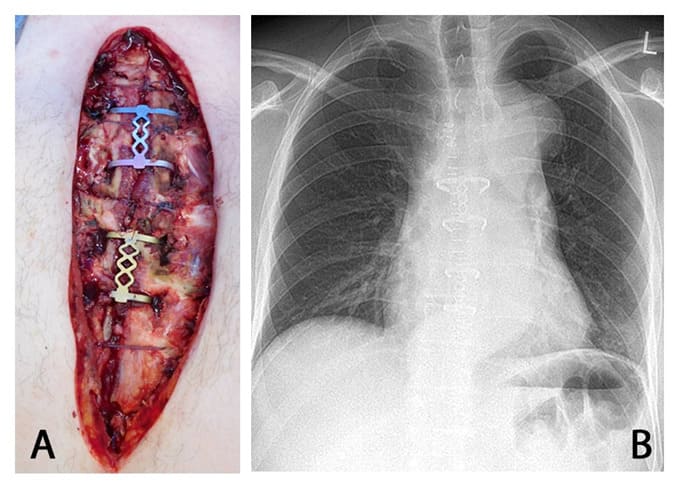

The internal thoracic artery is sufficiently far away in the corpus area that the sternum clips can be implanted without injuring the vessel. On average, the internal thoracic artery is 12.6 (4.7) mm and 16.3 (3.9) mm from the sternum. The minimum measured distance was 4.7 mm. This means that with preparation strictly lateral to the sternum, there is no risk of injuring the internal thoracic artery. There was no significant difference between the sides. It can thus be assumed that in most cases an appropriate sternum clip with two or three segments can be found. An intraoperative example of such a sternal reconstruction along with radiologic control is shown in Figure 6.

Figure 6: Intraoperative situs after sternum stabilization and postoperative chest x-ray.

(A) shows the intraoperative situs after sternum stabilization using two sternum clips (Medium-Large in 2nd and 3rd ICS, Small-Small in 4th and 5th ICS) and three PDS sutures. (B): postoperative control via chest x-ray, the sternum clips are properly placed.